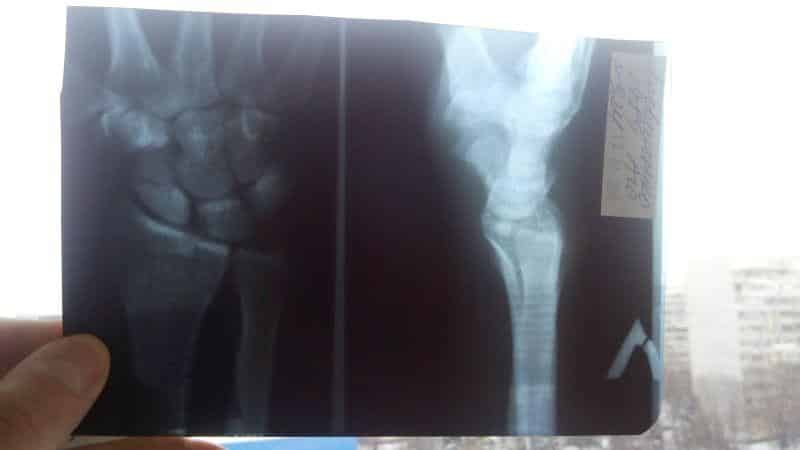

Первичная диагностика перелома основывается на визуальных данных. Для точного определения диагноза необходимы рентгенологические снимки в трех проекциях – прямой, боковой и 3D. Последняя позволяет четко увидеть профиль ладьевидной кости и линию перелома, которая не всегда заметна на рентгенограмме в прямом проекции.

Если клиническая картина указывает на перелом ладьевидной кости, но рентгенография не показывает его наличие, пациенту накладывается гипсовая повязка, а через несколько дней выполняется повторное рентгенологическое исследование.

В некоторых особенно сложных случаях для точного диагноза может быть использована процедура МРТ.